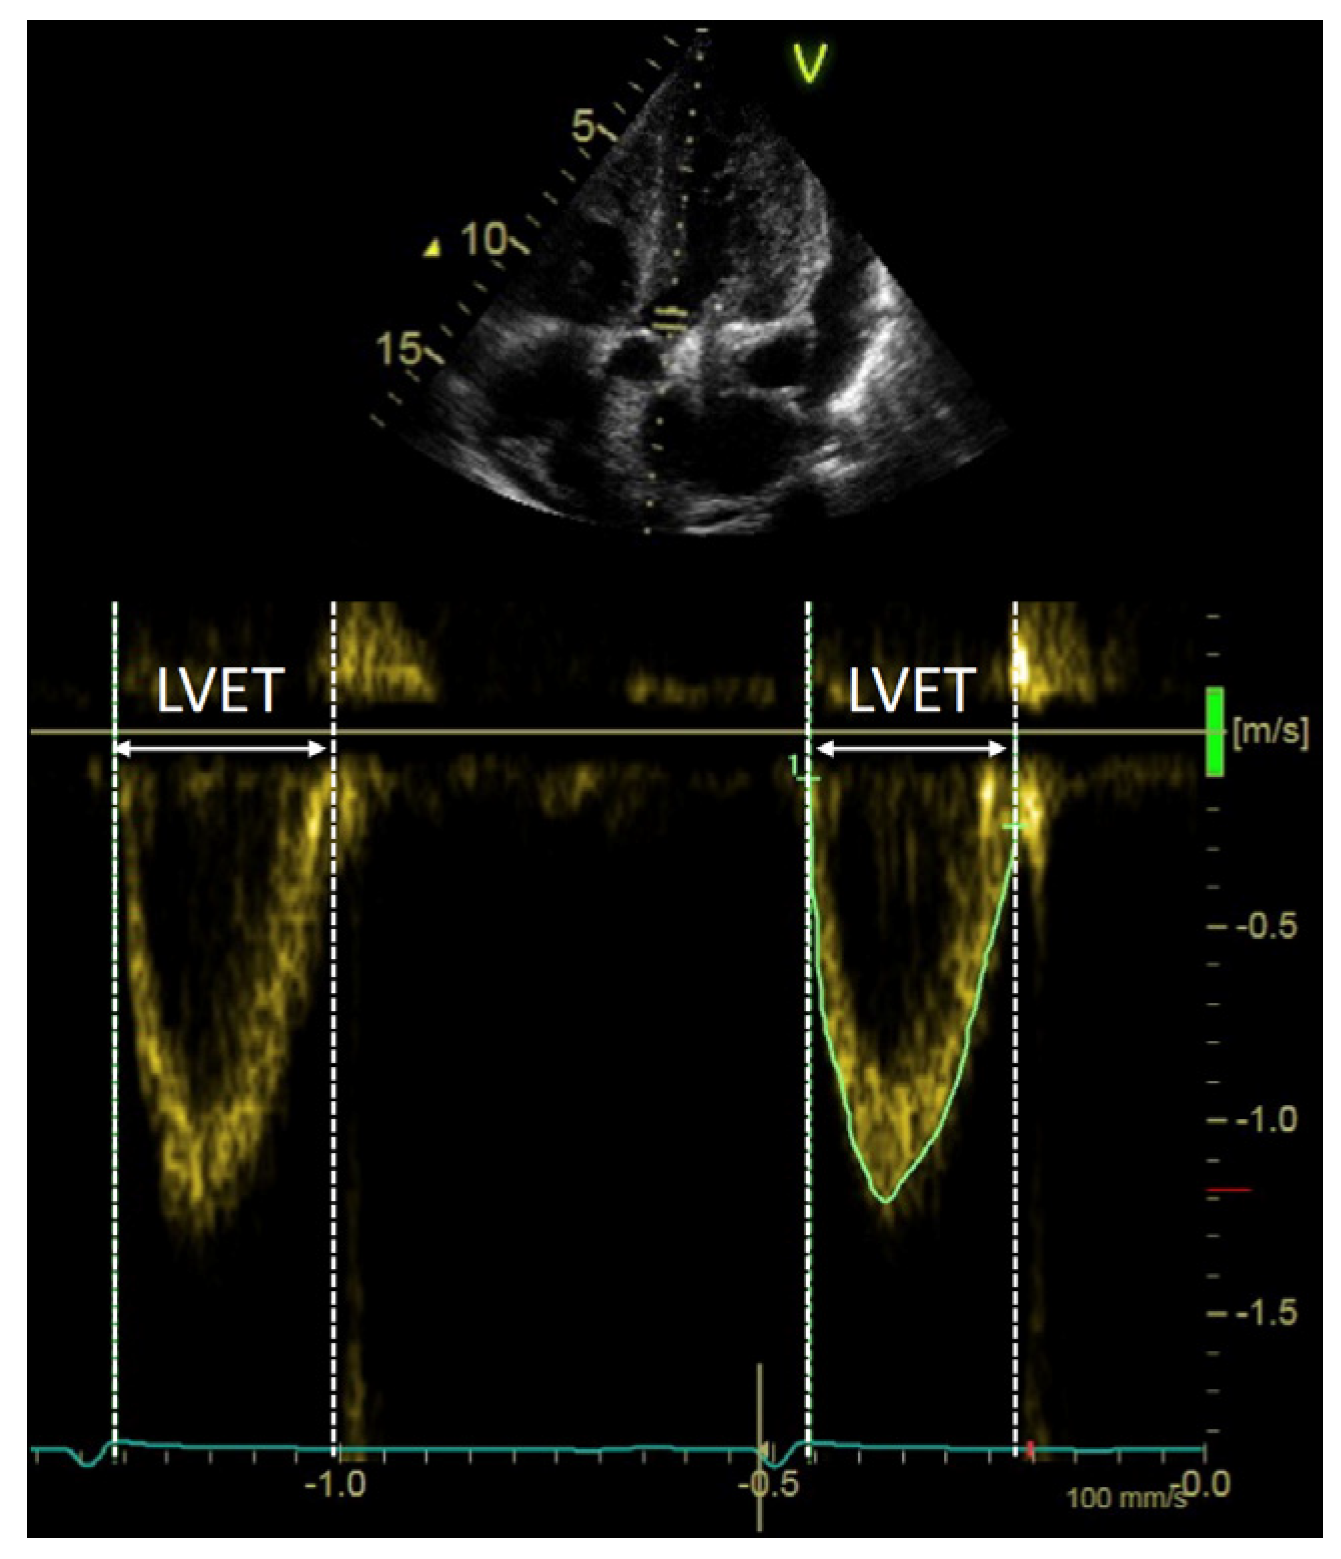

2.2. Echocardiographic Examination

2.4. LV Systolic Output Measures